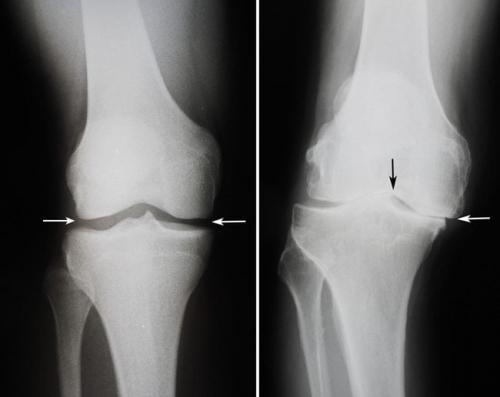

Двухстороннее отсутствие суставной щели.

Так выглядит на рентген-снимках артроз коленного сустава, упражнения для которого еще могут быть актуальны, потому что суставная щель не исчезла полностью.

На этом снимке суставу справа уже никакая гимнастика не поможет.